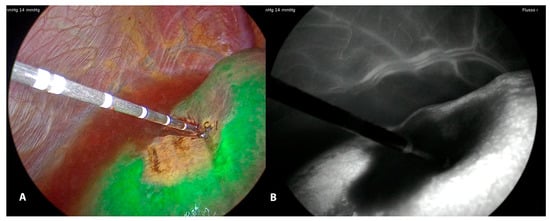

- In some procedures used during the laparoscopic thermoablation (IHVO) [26], it is possible to evaluate the ischemic effect of the occlusion of the vessel feeding the lesion. In this case, the ICG injection is performed immediately after the ablation of the vascular pedicle, and it is possible to visualize the area of the liver surface without IGC fluorescence (Figure 5).